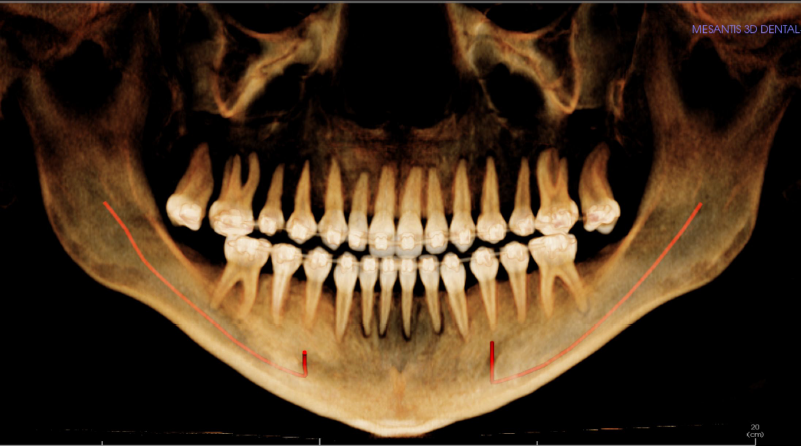

Diagnose:

Maxilläre Retrognathie, OK-Schmalkiefer, Hyperdivergenz, erschwerter Lippenschluss